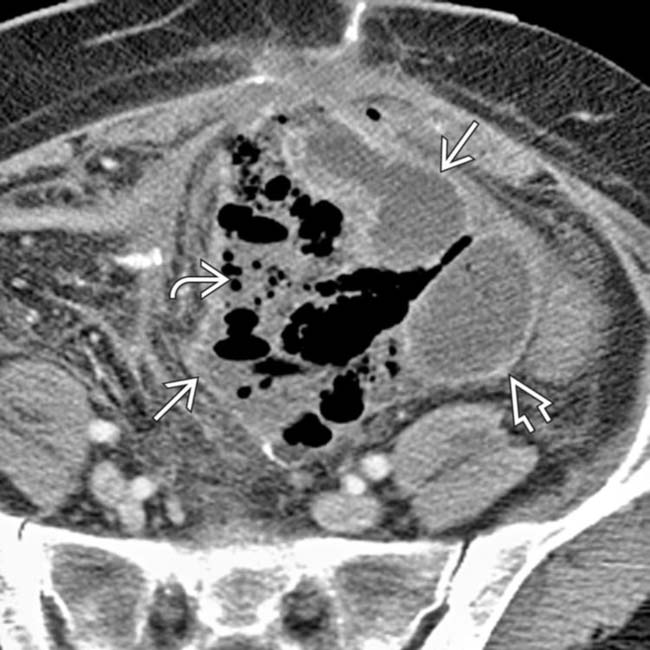

a, b, c: Abdominal CT scan showed a localized abscess formation above …

Case 3 -No evidence of intra-abdominal abscess. The thin, linear …

Abdominal Wall Abscess – Colon Case Studies – CTisus CT Scanning

Abdominal Abscess | Radiology Key

The Inaccessible or Undrainable Abscess: How to Drain It | RadioGraphics